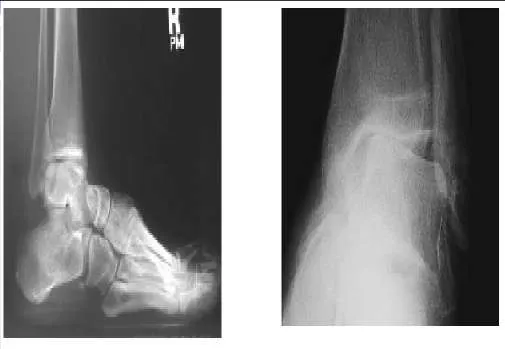

A patient sustained a fracture of the calcaneus 9 months ago. The fracture was treated with non-weight bearing and cast immobilization. The patient experiences constant pain and is unable to work. On examination, he has limited inversion, eversion motion of the foot, and lateral foot pain. Radiographs are presented. The recommended treatment is:

In the presence of stiffness of the subtalar joint, physical therapy modalities are unlikely to improve the foot function. For the young active worker, an early subtalar arthrodesis is the most reliable procedure to return him to work and an active lifestyle. A triple arthrodesis is contraindicated in the absence of painful transverse tarsal arthritis.